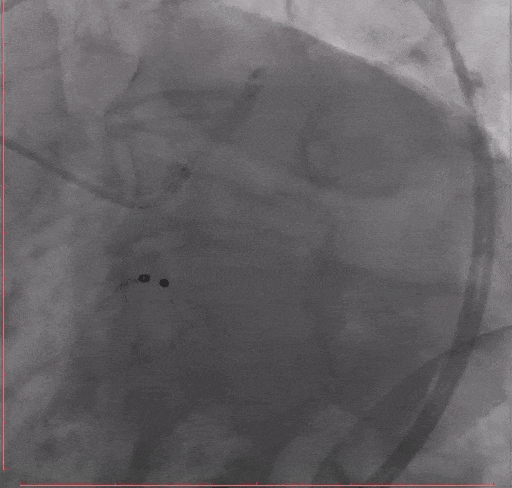

Step 4 旋磨后予以前降支支架植入

Step 5 左主干植入支架 回旋支开口予以切割+药物球囊